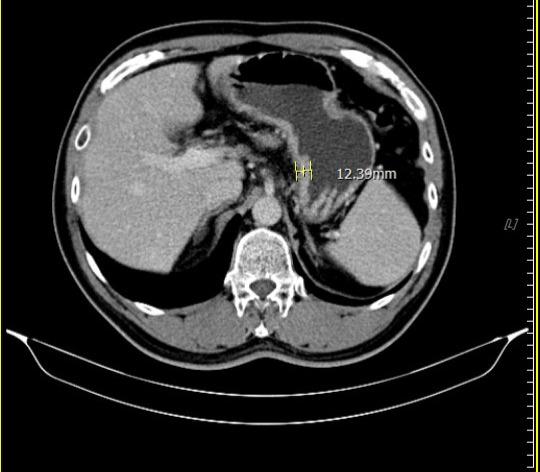

【視傳媒記者吉雄世高雄報導】53 歲男子因持續胃痛、食慾下降而日漸消瘦,至義大癌治療醫院血液腫瘤科饒坤銘副院長門診求診。原以為只是常見的腸胃不適,經檢查後,診斷第三期胃癌,腫瘤已明顯影響胃部功能,短短時間讓他體重減輕 10 公斤。突如其來的噩耗,讓病人與家屬瞬間陷入巨大的焦慮與無助。

在為期兩個月的術前免疫治療合併化療期間,病人雖出現噁心、掉髮、倦怠等副作用,但家人每日陪伴、鼓勵,使他能堅定完成療程。隨著治療進展,患者症狀逐漸改善,胃痛減緩、進食量增加、精神與體力明顯好轉,全家人的心情也從陰霾中逐步走出。

經義大醫療外科團隊進一步評估後,患者體況已達手術標準,並順利接受胃部腫瘤切除手術。手術後的病理報告更帶來令人振奮的結果:腫瘤組織中未發現殘存癌細胞,成功達成「病理完全反應」。得知結果的當下,患者與家屬喜極而泣,醫療團隊也深感欣慰,這不僅是治療上的成功,更是病人、家屬與醫療團隊共同努力的成果。